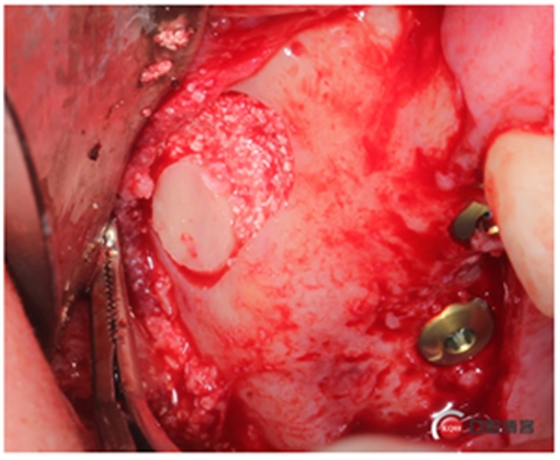

植入骨粉,這時候我們剛才取下的自體骨就派上用場了,加上小牛骨。

同期植入植體。

縫合,快!忒快了,二十分鐘搞定。不要懷疑,這是真的,參加過我的學(xué)習(xí)班的老師都看過我的很多視頻,超級安全、超級快。